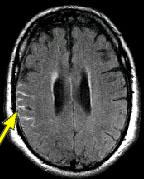

IMAGING FINDINGS: The CT was performed on AIC’s new 16-slice helical multi-slice CT (MSCT). Both routine single-slice and thin-section helical scans were obtained and 3D/Multiplanar images were performed on the Advanced 3D workstation. Fig. 1 shows an image at the level of the lateral ventricles with possible high density within the sulci on the right (arrow). To confirm this finding, an MRI with contrast was then obtained on AIC’s 1.5-Tesla high-field, short-bore Siemens MRI. Fig. 2a-b are T2-weighted images at the same level showing NO definite abnormality. T1-weighted images (not shown) were also negative. The post-contrast images (not shown) showed NO abnormal enhancement in this region, either. Diffusion-weighted images were also negative. However, Fig. 3a-b, which are FLAIR images, demonstrate clear hyperintensity within multiple sulci involving the right temporo-parietal area (arrows).

DIAGNOSIS: The FLAIR images are compatible with Subarachnoid disease. The Differential Diagnosis includes: (1) Subarachnoid Hemorrhage (SAH); (2) Meningitis; (3) Infarct; (4) Flow Artifact. Lack of enhancement is against meningitis. Acute infarct was ruled out on the basis of negative Diffusion MRI and lack of cytotoxic edema on the FLAIR images. Focal abnormality is against flow artifact (which is more diffuse and usually in the posterior fossa on FLAIR images). The clinical history of trauma and the high-density on CT and hyperintensity on FLAIR images within the sulci are diagnostic of Acute Post-traumatic Subarachnoid Hemorrhage (SAH).

DISCUSSION: MRI FLAIR imaging is the modality of choice for diagnosis of supratentorial SAH. In the posterior fossa, however, CT is superior due to flow artifacts on FLAIR images in the peripontine/ambient cisterns. A combination of CT and MRI would be ideal to optimize detection sensitivity.